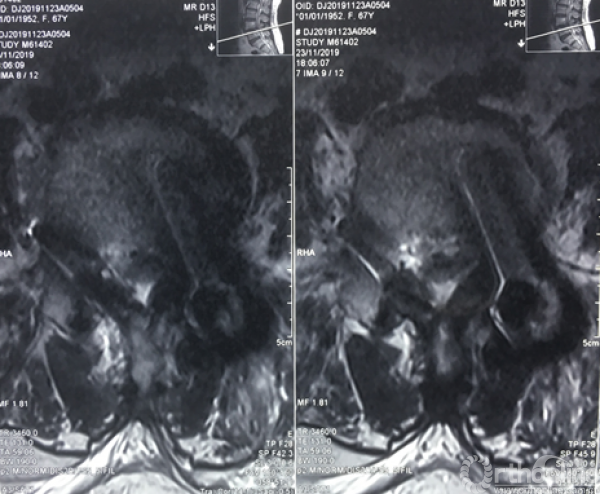

术前腰椎核磁共振横断面